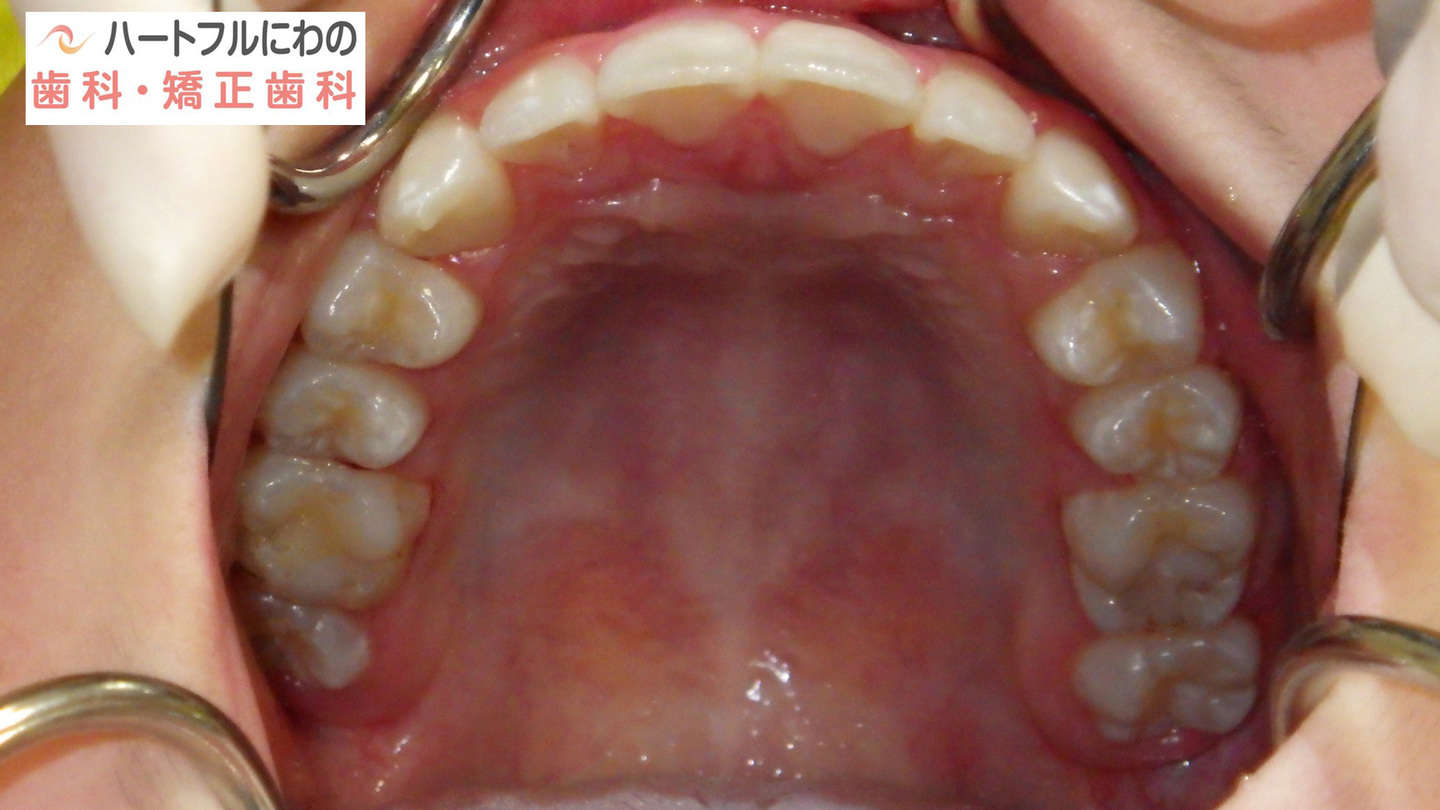

奥歯と前歯の前後的位置関係は大きく改善し、正常になりました。

細かい部分の修正や緊密な咬み合わせを作るための二期治療(仕上げ)は一年以内で終了予定です。